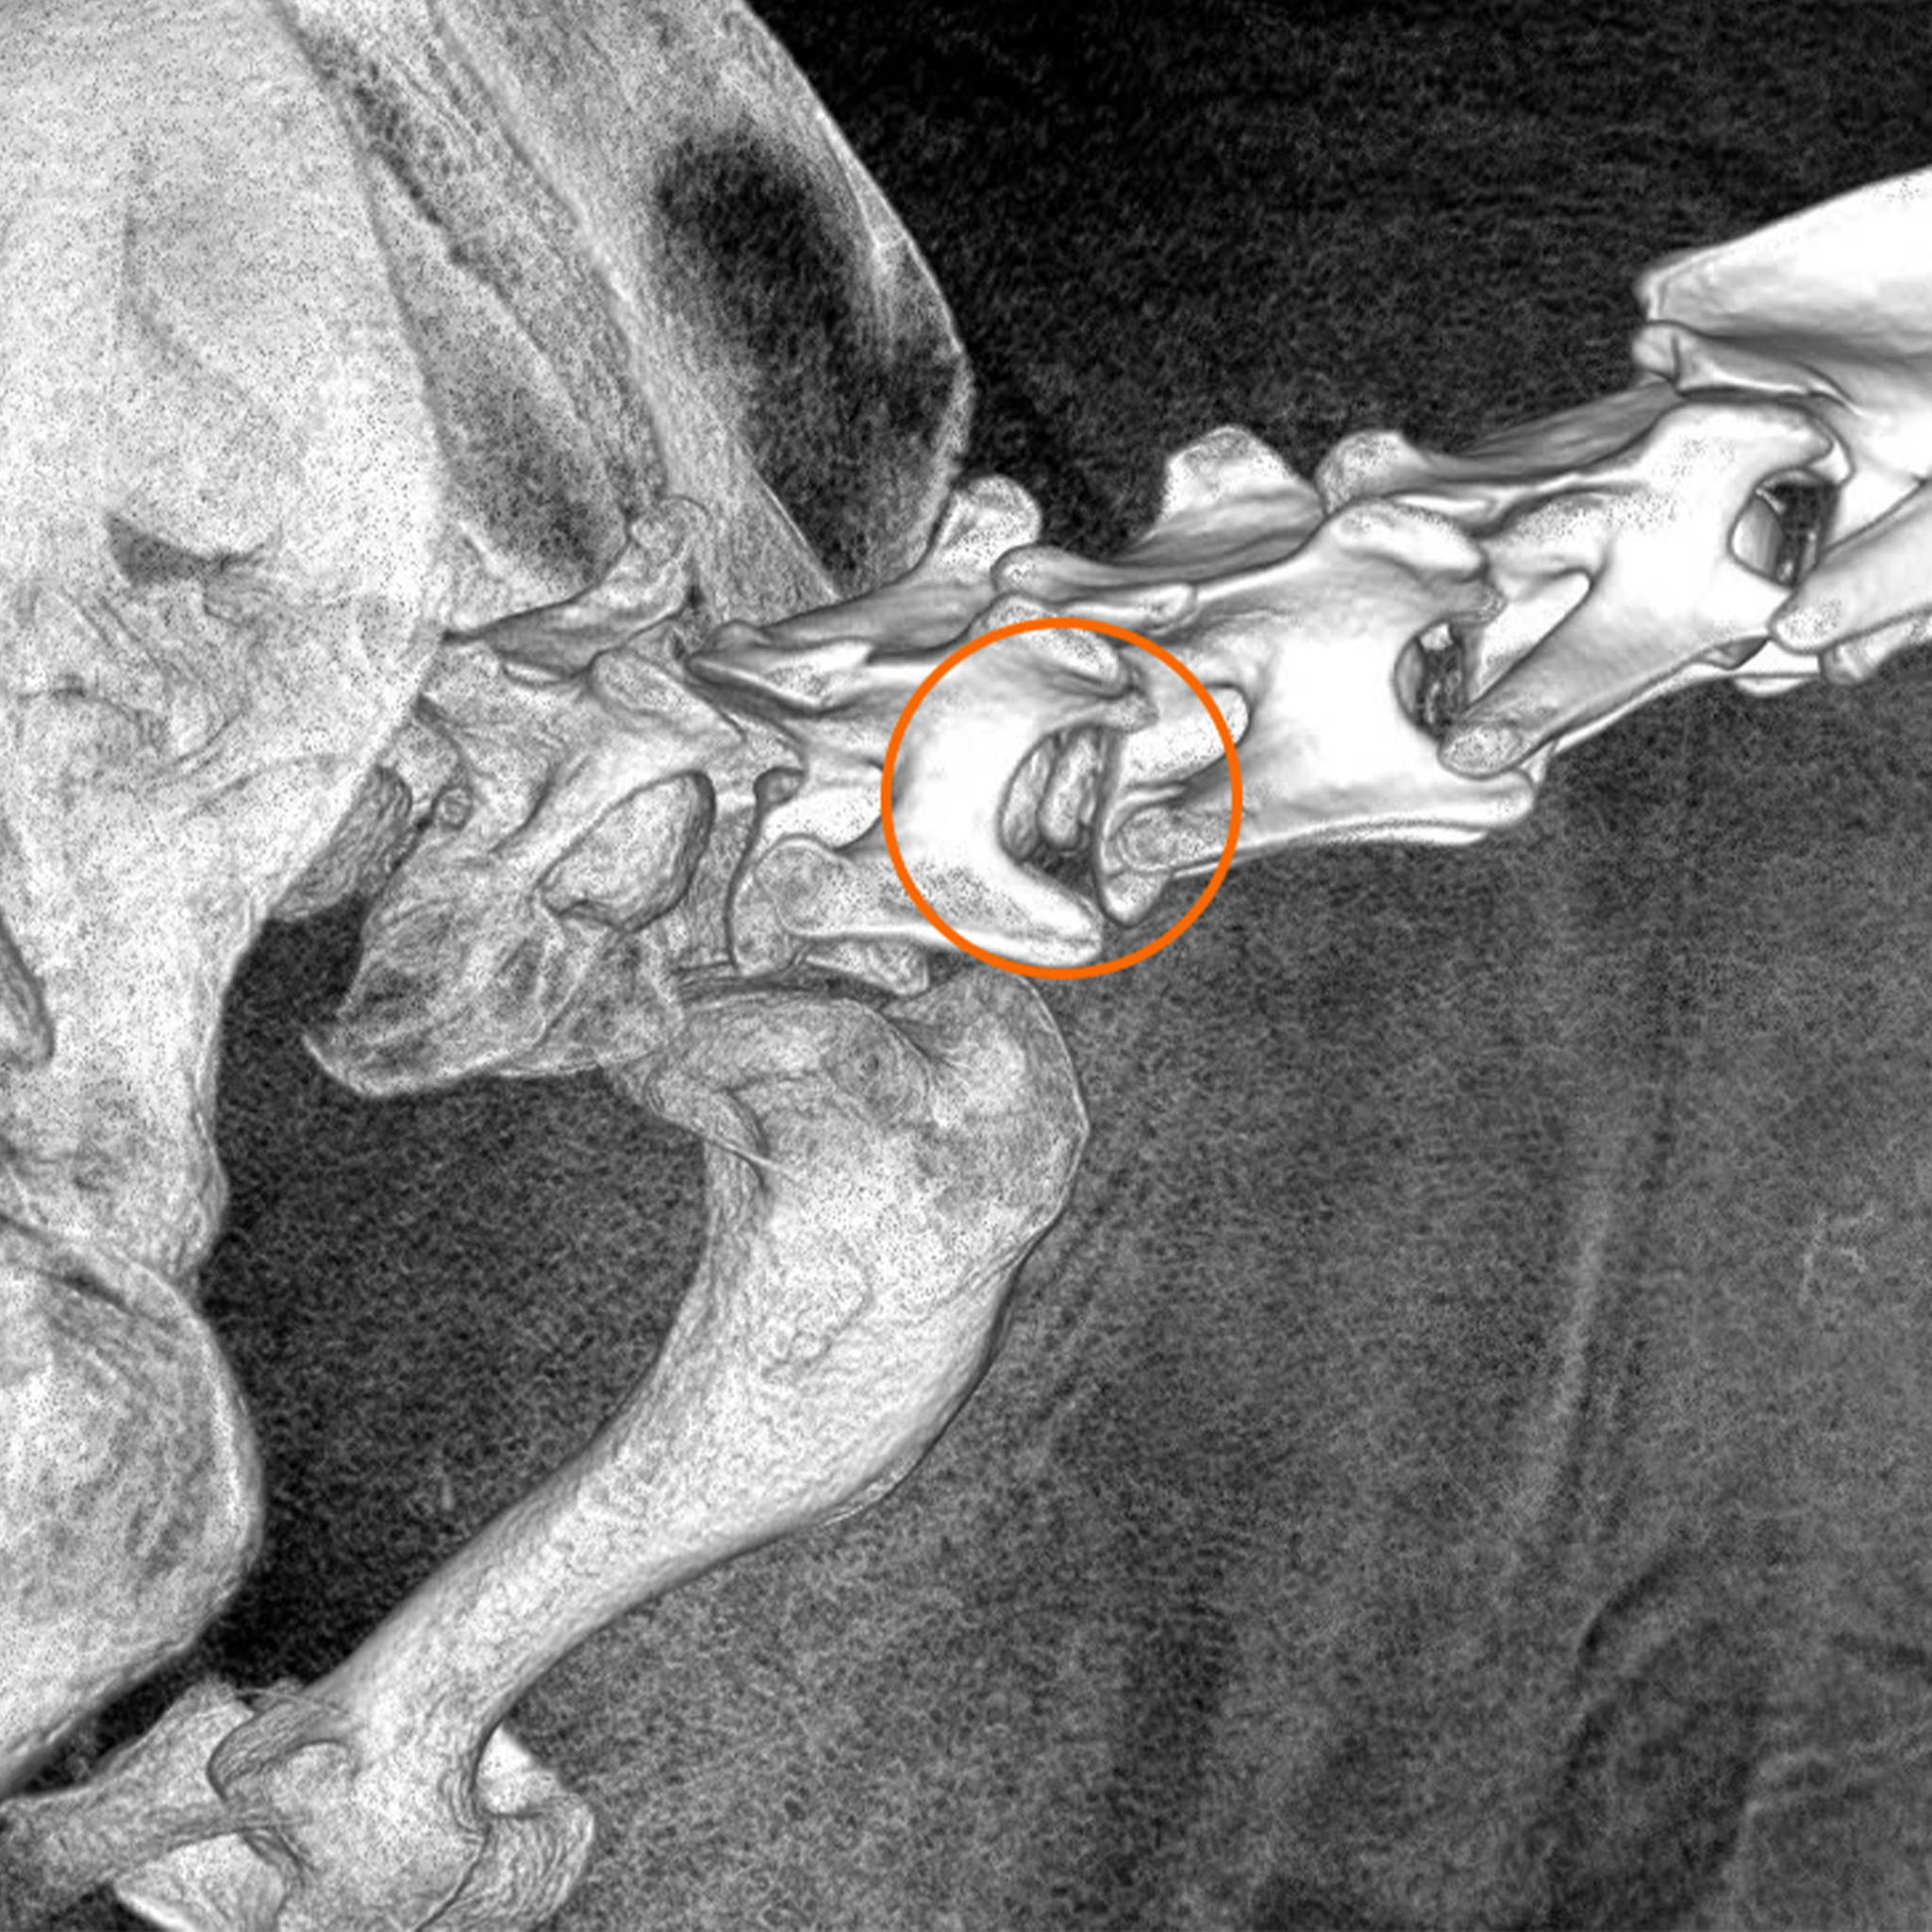

Dịch vụ phẫu thuật cố định cột sống và thoát vị đĩa đệm ở chó mèo – Chẩn đoán và điều trị bệnh lý đĩa đệm C3 – C4 ở bạn chó Bomi

Báo cáo ca lâm sàng: Thoát vị đĩa đệm C3 - C4 ở chó Bomi